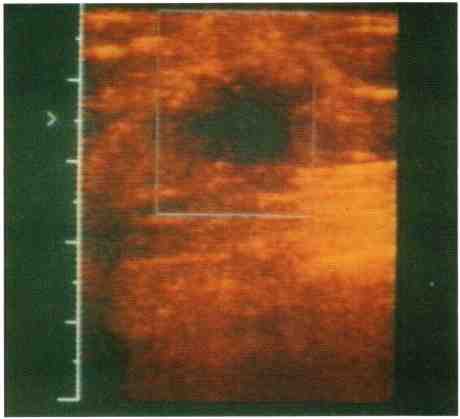

ECOGRAFIA

L’esame ecografico del seno viene eseguito con tecnica manuale, mediante sonda a frequenze elevate. È indicata nell’approfondimento diagnostico delle lesioni mammarie non chiarite dall’esame clinico e dalla mammografia e può essere impiegata in presenza di lesioni precliniche per il reperimento preoperatorio e la biopsia mirata.

Possiede una elevata specificità per le lesioni cistiche che possono trovare guarigione e diagnosi attraverso l’agoaspirazione del materiale liquido contenuto in esse.

La sensibilità complessiva per cancro è mediamente dell’80-90%, anche se un confronto con altri tests quali l’esame clinico e la mammografia non è possibile, trattandosi per l’ecografia di un impiego di secondo livello su casistiche altamente selezionate su base clinicoradiologica.